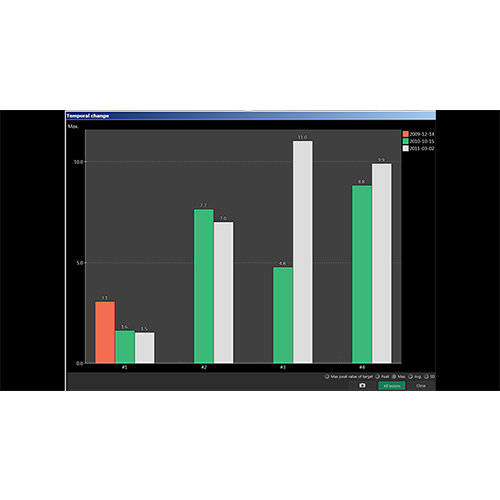

Better grasp of treatment progress by comparing scans over time

Side-by-side comparative assessment for pre- and post-operative scans.